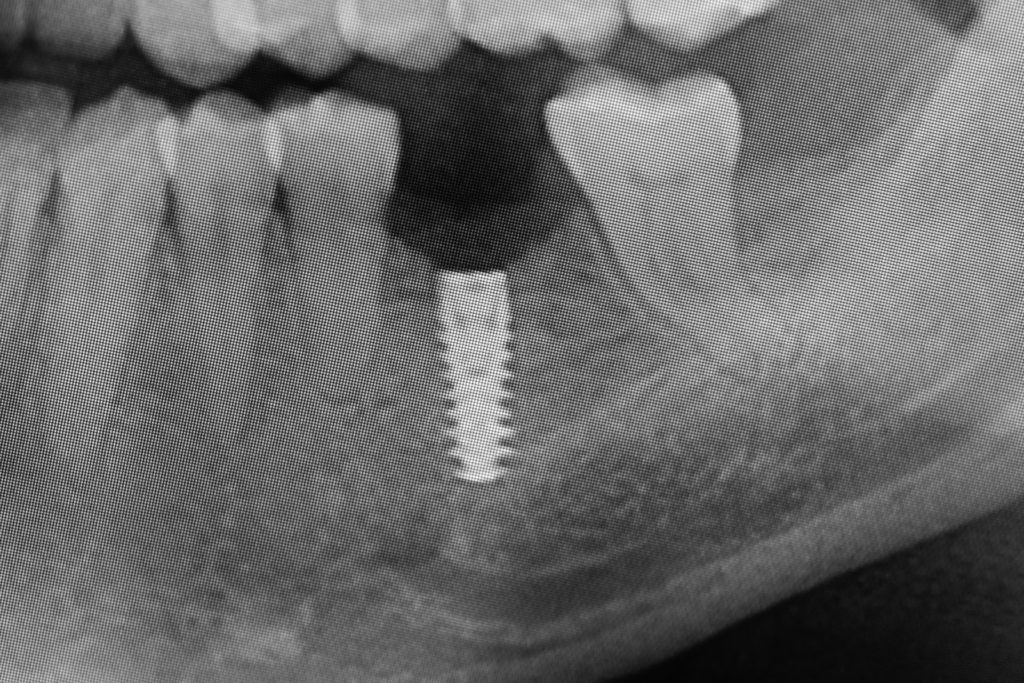

Przed podjęciem leczenia należy określić stopień zaniku kości szczęk oraz żuchwy. W tym celu przeprowadza się badanie kliniczne oraz odpowiednią diagnostykę obrazową pacjenta. Uwzględnia ona zdjęcie panoramiczne OPG jako podstawę dwuwymiarowego obrazowania podłoża kostnego oraz możliwe jest badanie tomograficzne CT lub bardziej precyzyjna tomografia stożkowa CBCT. Opcjonalnie wykorzystywana diagnostycznie tomografia pozwala na bardziej wnikliwą ocenę stopnia zaniku kości w trójwymiarowym, przestrzennym obrazie.

Procedury te są stosowane w sytuacji niedostatecznej ilości kości, skutkującej odsłonięciem gwintu, podczas gdy wszczepiamy implanty stomatologiczne lub też jako zabiegi poprzedzające ich wprowadzenie.​

• Użycie drobin kości własnej do pokrycia ubytków na niewielkim obszarze, jak obnażenia gwintu implantu podczas implantacji, obnażenie korzeni zęba czy furkacji korzeniowych. Wiórki kostne pobierane są podczas zabiegu specjalnymi aplikatorami (skrobaczkami) z powierzchni kości szczęk i żuchwy.

Zabieg odbudowy zębodołu powinno się wykonać możliwe jak najszybciej po usunięciu zęba. Jego celem jest odbudowa naturalnej objętości kości w miejscu utraconego zęba, a następnie szybkie wprowadzenie implantu. Najlepsze rezultaty uzyskuje się przy zastosowaniu biomateriału w formie bloczków kolagenowych lub granulatu, które dają trwałe efekty odbudowy oraz optymalną funkcję i estetykę odtworzonych koron zębów na wszczepionym implancie.

Metoda rekonstrukcji kostnej w oparciu o indywidualnie drukowane siatki z tytanu dla implantacji wszczepów śródkostnych stosowana jest najczęściej jako dwuetapowa. W pierwszym etapie odbudowywana jest kość, natomiast implanty wszczepiane są po okresie 4–6 miesięcy. Na wgojenie implantów oczekujemy od 4 do 6 miesięcy w zależności od miejsca ich lokalizacji. Siatka tytanowa po spełnieniu swojej funkcji rusztowania dla odbudowującej się kości jest następnie usuwana w dniu wszczepienia implantu. Jeżeli kość spełnia odpowiednie warunki, istnieje możliwość zastosowania modyfikacji siatki tytanowej, która umożliwia jednoczesne wprowadzenie implantów wraz z odbudową kostną. Wariant ten skraca czas od pierwszego zabiegu do wykonania gotowych koron protetycznych na wprowadzonych implantach.